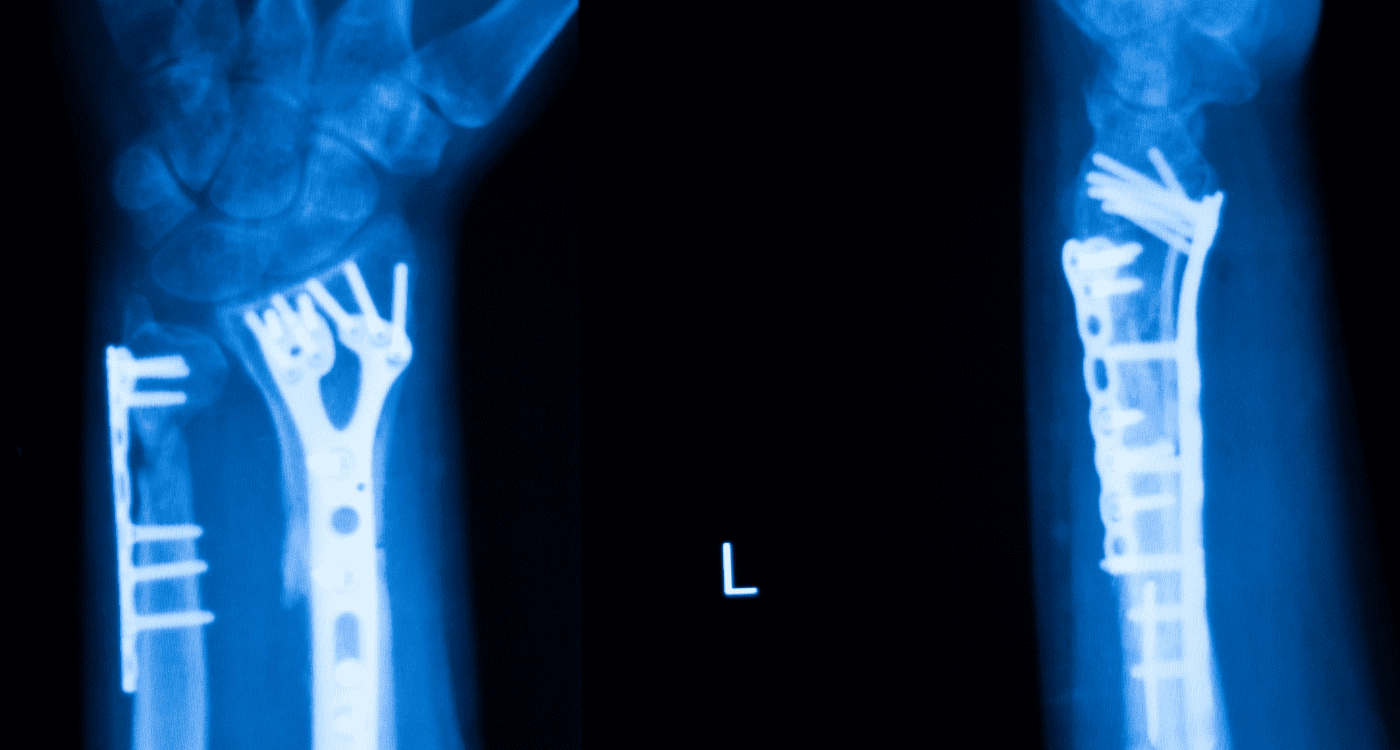

Cualquier lesión de ligamentos puede manifestarse inicialmente como esguinces de diversos grados, pero su evolución depende de un diagnóstico preciso. Es fundamental descartar si el traumatismo ha provocado también una lesión de menisco o si el dolor articular es consecuencia de lesiones traumáticas que involucran el hueso. En nuestra consulta en Saltillo, evaluamos si cuadros de tendinitis o bursitis están enmascarando una inestabilidad mayor que requiera intervención quirúrgica o biológica avanzada.